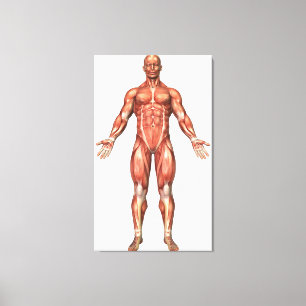

Lienzo Ilustracion médico del sistema muscular masculino

Precio 187,00 €